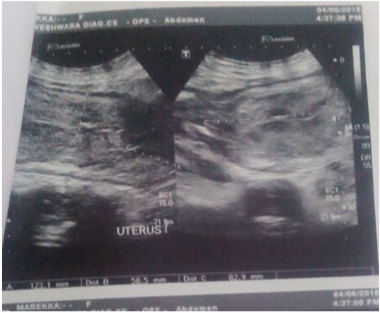

Intraoperatively bladder was edematous and pulled up [Table/Fig-3], after separating uterovesical fold of peritoneum bladder was pushed down [Table/Fig-4]. Lower uterine segment was stretched out. Khers incision was given on lower uterine segment and a dead term female baby of weight 2.4kg was extracted as breech. Placenta was dichorionic diamniotic. No uterine malformations were there. Bilateral broad ligament haematomas approximately of 8x8 cm were noted which were increasing in size after extraction of baby [Table/Fig-5,6], on both sides haematomas were evacuated and drained along with bilateral uterine artery ligation was done. A drain was kept in pouch of douglas and abdomen was closed in layers. One unit of whole blood was transfused intraoperatively and two unit of whole blood was transfused postoperatively. She was monitored in ICU (intensive care unit) for 72 hours. Monitoring patient’s pulse, blood pressure, temperature, respiratory rate, oxygen saturation and urine output (Foley’s catheter) every 4 hours for the first 48 hours, then every 6 hours afterwards. Intravenous prophylactic antibiotics (ceftriaxone 1gm BD, metronidazole 500 mg TDS) were prescribed for 7 days. An ultrasound scan was done on her third postoperative day showed full resolution of broad ligament haematoma [Table/Fig-7]. Foley’s catheter was retained in bladder for 14 days to prevent fistula because of avascular necrosis. The woman recovered well and was discharged home 14 days later. At discharge, a repeat scan confirmed no recurrence of the haematoma.

Postoperative day 3 abdomino pelvic scan showed involuting uterus, full resolution of broad ligament haematoma